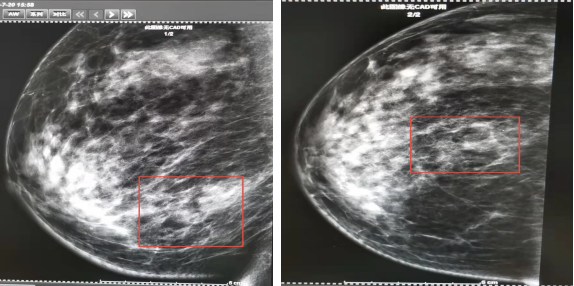

钼靶(2021-07-20,图2):右乳房下象限肿块影,形态不规则,边界不清,边缘可见分叶,病灶内多发点状、粗点状钙化灶,病灶大小约38*17mm。右腋前份显示增大淋巴结。

图2.右乳钼靶影像

钼靶(2021-12-15):右乳房下象限肿局部腺体稍紊乱,可见条片状稍高密度影,伴多发点状,粗点状钙化灶。双腋窝未示明显肿大淋巴结影。

图6.2021-07-20钼靶图(左)vs2021-12-15钼靶图(右)